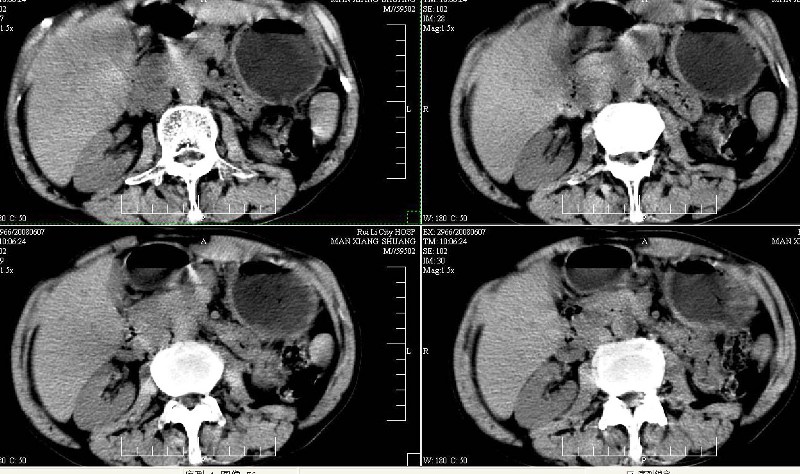

标题: CT13937:M,42A.腰疼一周。

dr:l4骨质破坏,转移可能。

ct:肝癌腰椎转移。临床医生:肝脏、骨转移,肿瘤来自?前列腺?!

腰椎间盘膨出+突出,椎体考虑为转移、退变。

支持肝癌伴椎体转移瘤。腹膜后建议ct增强,好象有增大的淋巴结。

1、支持肝癌肝内及腰椎转移。